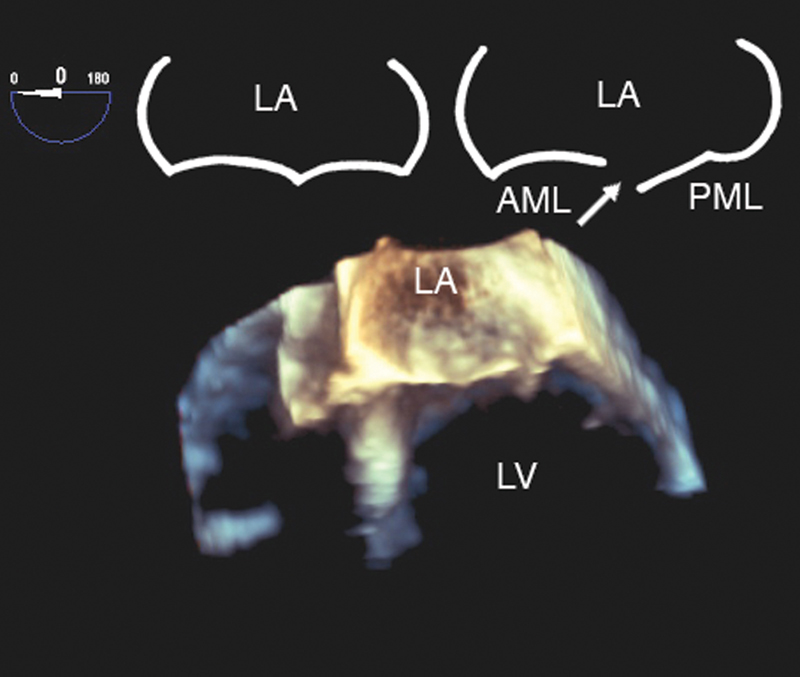

فحوصات تشخيصية لبعض امراض القلب والشرايين التاجية